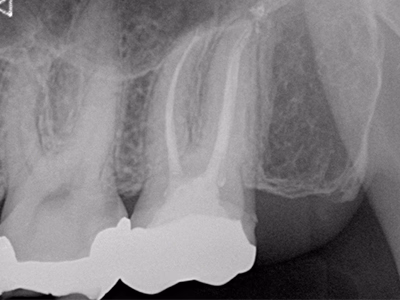

他院で抜髄処置後も咬合時違和感が続く(破折リーマー残存の情報あり)

治療内容

- ① マイクロスコープ+ラバーダム下で再根管消毒

- ② CTで破折器具の位置・長さを確認し破折リーマー除去

- ③ 症状改善を確認し根管充填

- ④ ファイバーコア築造+セラミック装着

約2ヶ月(1回の治療:1~2時間)

- マイクロエンド 132,000円

- 破折リーマー除去 33,000円

- ファイバーコア 22,000円

- 仮歯 6,600円

- セラミック冠 165,000円

慢性根尖性歯周炎の再発可能性/術後の痛み・腫脹・出血

破折器具除去と無菌的消毒を徹底し、緊密充填と精密補綴を実施。長期経過で良好。